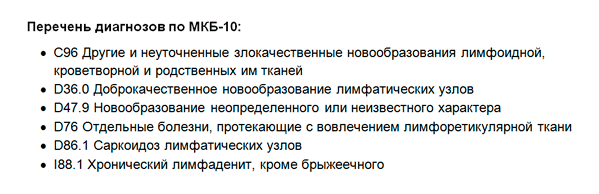

Код мкб 10 атерома головы

Код мкб 10 атерома головы 109 фото